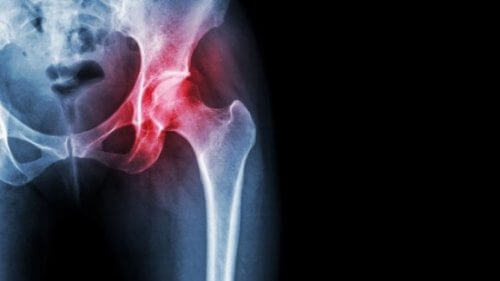

Necrose avascular da cabeça femoral

A necrose avascular, como toda necrose, é causada pela falta de suprimento sanguíneo para os tecidos. Nesse caso em particular, afeta os ossos, o que tem uma série de consequências bastante graves.

Como alguns artigos apontam, como Coxalgia crónica: necrosis avascular de la cabeza femoral, a necrose avascular não é muito comum. No entanto, isso não significa que não mereça uma atenção especial, pois as suas sequelas são graves e os riscos para os pacientes são muito altos.